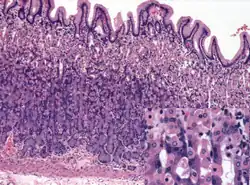

Microanatomy

Wall

Like the other parts of the gastrointestinal wall, the human stomach wall from inner to outer, consists of a mucosa, submucosa, muscular layer, subserosa and serosa.[19]

The inner part of the stomach wall is the gastric mucosa a mucous membrane that forms the lining of the stomach. The membrane consists of an outer layer of columnar epithelium, a lamina propria, and a thin layer of smooth muscle called the muscularis mucosa. Beneath the mucosa lies the submucosa, consisting of fibrous connective tissue.[20] Meissner's plexus is in this layer interior to the oblique muscle layer.[21]

Glands

The mucosa lining the stomach is lined with gastric pits, which receive gastric juice, secreted by between 2 and 7 gastric glands. Gastric juice is an acidic fluid containing hydrochloric acid and digestive enzymes.[24] The glands contains a number of cells, with the function of the glands changing depending on their position within the stomach.

Within the body and fundus of the stomach lie the fundic glands. In general, these glands are lined by column-shaped cells that secrete a protective layer of mucus and bicarbonate. Additional cells present include parietal cells that secrete hydrochloric acid and intrinsic factor, chief cells that secrete pepsinogen (this is a precursor to pepsin- the highly acidic environment converts the pepsinogen to pepsin), and neuroendocrine cells that secrete serotonin.[25]

Glands differ where the stomach meets the esophagus and near the pylorus.[26] Near the gastroesophageal junction lie cardiac glands, which primarily secrete mucus.[25] They are fewer in number than the other gastric glands and are more shallowly positioned in the mucosa. There are two kinds - either simple tubular glands with short ducts or compound racemose resembling the duodenal Brunner's glands. Near the pylorus lie pyloric glands located in the antrum of the pylorus. They secrete mucus, as well as gastrin produced by their G cells.[27]